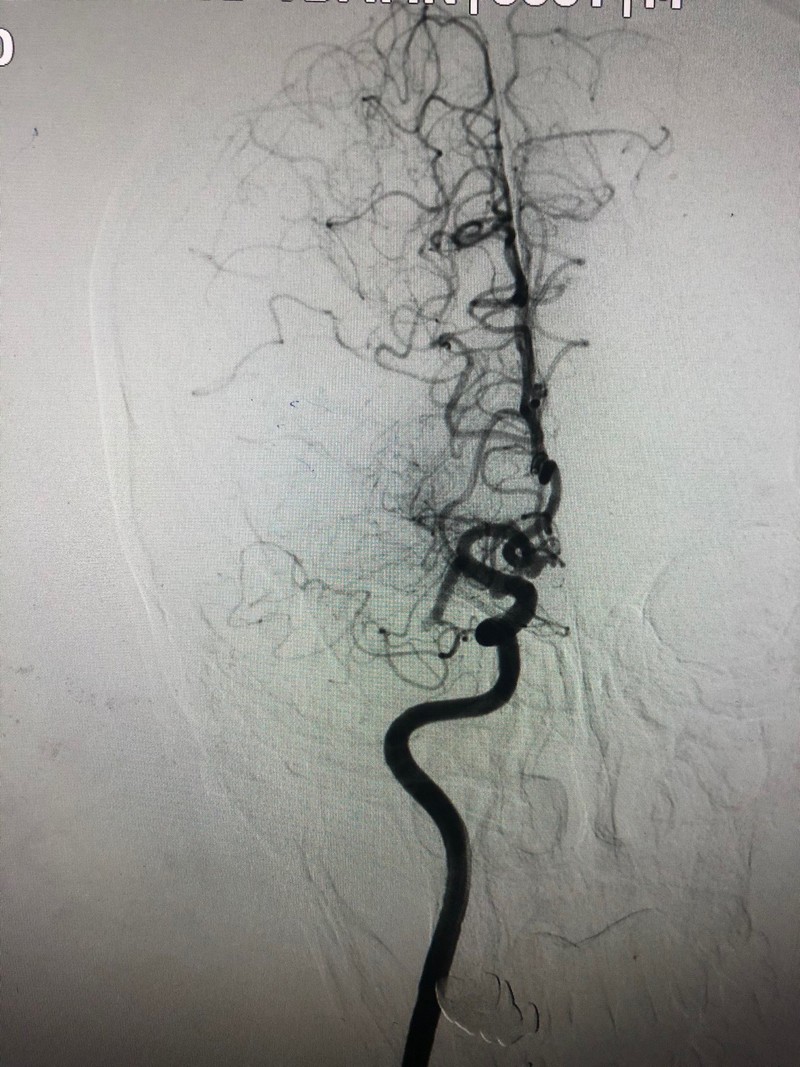

Sau khi tiếp nhận bệnh nhân, các bác sĩ đã chụp cắt lớp vi tính sọ não. Kết quả cho thấy bệnh nhân bị tắc động mạch não giữa bên phải. Ngay lập tức, người bệnh đã được can thiệp lấy huyết khối qua đường động mạch sau tai biến giờ thứ 6).

Chụp tắc động mạch não giữa đoạn M1 phải. Ảnh: BVCC